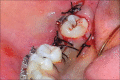

The interdisciplinary collaboration of periodontics and orthodontics has allowed teeth to be moved 2-3 times faster, reducing the time required for traditional orthodontic therapy considerably. Periodontally accelerated osteogenic orthodontics (PAOO), also known as Wilckodontics, is a combination of a selective decortication facilitated orthodontics and alveolar augmentation. With this technique, there is no dependence on the pre-existing alveolar volume. This case report describes the treatment of permanent mandibular molar protraction in a 14-year-old patient undergoing orthodontic therapy using PAOO with piezosurgery.